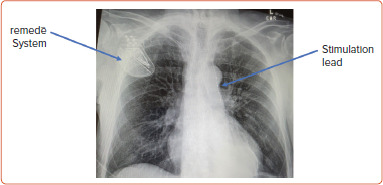

Central sleep apnoea (CSA) is a common comorbidity in patients with heart failure. Due to its insidious and chronic nature, CSA often remains unrecognised. Patients with CSA typically present with symptoms, such as daytime fatigue, recurrent heart failure decompensations and cardiac arrhythmias. Although the pathophysiology of CSA is not yet fully understood, the most widely accepted theory suggests that fluctuations in PaCO2 levels, particularly crossing the apnoeic threshold, play a central role in its development. CSA is associated with various changes, including activation of the sympathetic nervous system, neurohormonal disturbances and haemodynamic perturbations, all of which contribute to increased morbidity and mortality. Transvenous phrenic nerve stimulation (TPNS) has been demonstrated to be a safe and effective therapy for reducing the apnoea-hypopnoea index and improving both left ventricular ejection fraction and quality of life in patients with CSA. These benefits have been validated in randomised clinical trials (RCTs). New methods of analysing RCTs were recently introduced. Applying the win ratio method in a post hoc analysis of the primary RCTs evaluating TPNS suggested that TPNS may also contribute to reduced mortality and fewer heart failure hospitalisations. In this article we explore the pathophysiology of CSA and evaluate the existing evidence on therapeutic options, with a particular focus on TPNS.